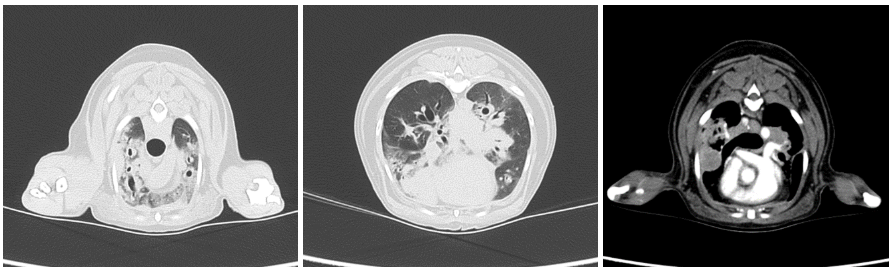

CT검사 상에서 폐엽 전체에 걸친 침윤을 확인하였으며 일부엽에서는 조영증강을 동반한 결절도 확인되었습니다.

해당 결절은 종양가능성 혹은 심한 염증으로 인한 육아직 형성 등으로 생각이 되었어서 예정대로 폐세척 검사(BAL)도 진행하였습니다. ▼